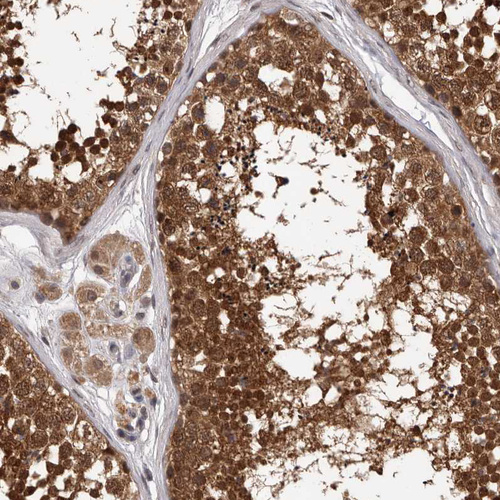

Immunohistochemical staining of human cerebral cortex shows moderate to strong nuclear positivity in neurons.